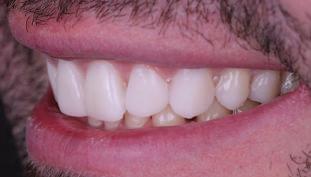

тация на долната челюст. Дъга GUMMETAL с tip-back извивки бе поставена в долната челюст за ниве лиране кривата на Шпее. Случаят бе финализиран с 19x25 SS дъги в горната и долната зъбна дъга за координиране. Преди да се изготви финалният восъ чен моделаж, естетичните и лицеви те характеристики бяха анализирани с помощта на дигитален дизайн на ус мивката, за да се създаде мок-ъп, чии то форма и размери да бъдат одобрени от пациента. Бе оценена фонетиката и бяха заснети лицеви снимки и видеа. Зъ бите бяха изпилени, като препарация та бе изцяло водена от функционалния восъчен моделаж, прехвърлен в устата на пациента. След препарацията восъч ният моделаж бе напаснат и насложен върху препарационния модел и бе фрезо ван от e-max multi bl 1. Циментирането на финалните конструкции бе направе но при изолация с кофердам, следвайки адхезивния протокол. След циментирането бе направено проследяване на оклузията чрез снема не на отпечатъци, монтиране на моде лите в артикулатор в окончателната интеркуспидация и внимателно прове ряване за наличие на блокажи при воде ни движения.

След стабилизира не на ставите и долната челюст в те рапевтична позиция постигнах орто донтски премествания и скелетни ко рекции, които обикновено са възмож ни единствено посредством ортогнат на хирургия. Преминах от аналогов мо дел на работа към изцяло дигитален, за да се хармонизира лицевата естетика чрез Digital Smile Design, като същевре менно обаче изработих функционален аналогов восъчен моделаж и на двете че люсти, за да мога да приложа оклузална та концепция на Славичек. След което напаснах препарациите с аналоговия во съчен моделаж при изцяло дигитални ус ловия с цел фрезоване на короните. Всич ки тези комбинации правят случая из ключително комплексен. В крайна сметка този сложен случай бе лекуван с най-добрата възможна ком бинация от възможности, които ана логовият и дигиталният свят предла гат, за да се постигне красота, която е следствие от отлична функция. ОКЛУЗАЛЕН „БАЛЕТ“ С РОЗОВАТА ЕСТЕТИКА Клиничен случай, победител в категория „Комплексно естетично възстановяване“ в конкурса „Усмивка на годината 2022“ Преди След

планта бе поставена временна коронка (фиг. 10 и 11), докато бъде изготвена окончателна та. Бе постигнат отличен кра ен резултат. Меките тъка ни около импланта напълно заздравяха, което доприне се за перфектната хармония между бяла и розова естетика (фиг. 12–15).